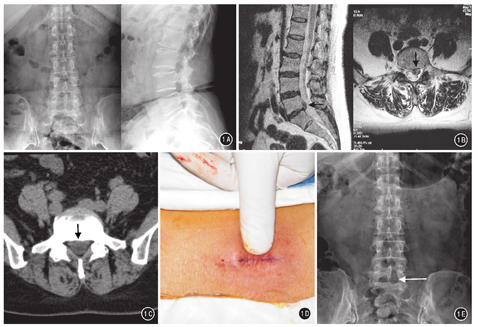

采用德国Joimax椎间孔镜手术系统。患者取俯卧位,C形臂X线机确定病变椎间隙的体表投影,取L5/S1椎间盘水平线上、脊柱后正中线患侧旁开2 cm为进针点,1%利多卡因分层浸润麻醉。穿刺定位针,沿穿刺针插入套管、工作套管,置入椎间孔镜,显露神经根及硬膜囊,摘除突出间盘组织。低温等离子系统射频止血、髓核消融,松解神经根周围粘连组织、纤维环成形。见图3。